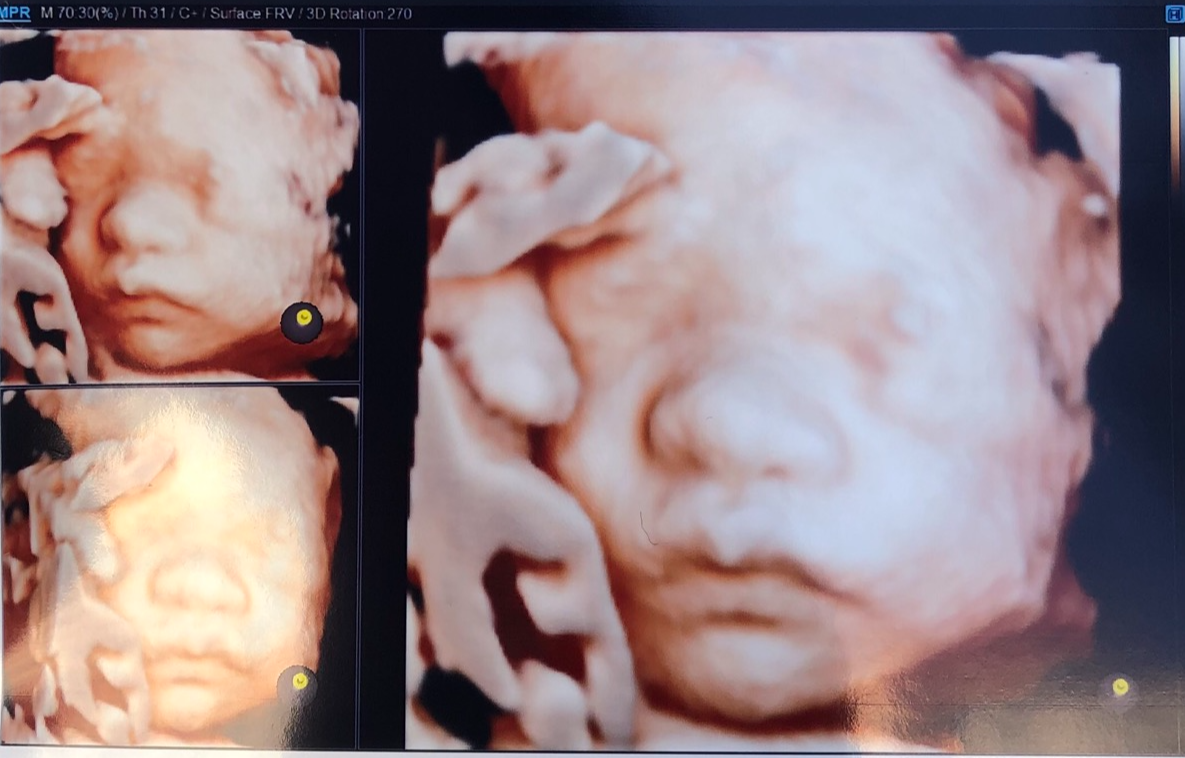

※12~16주: 입체 초음파 (선택사항)

입체 초음파를 통해 우리 아이의

※20~24주: 정밀 초음파

초음파로 정밀하게 태아를 살펴 구조적인 기형 여부 및 정상발달 여부를 확인한다.

이때 우리 아이를 얼굴을 입체로 볼 수 있다